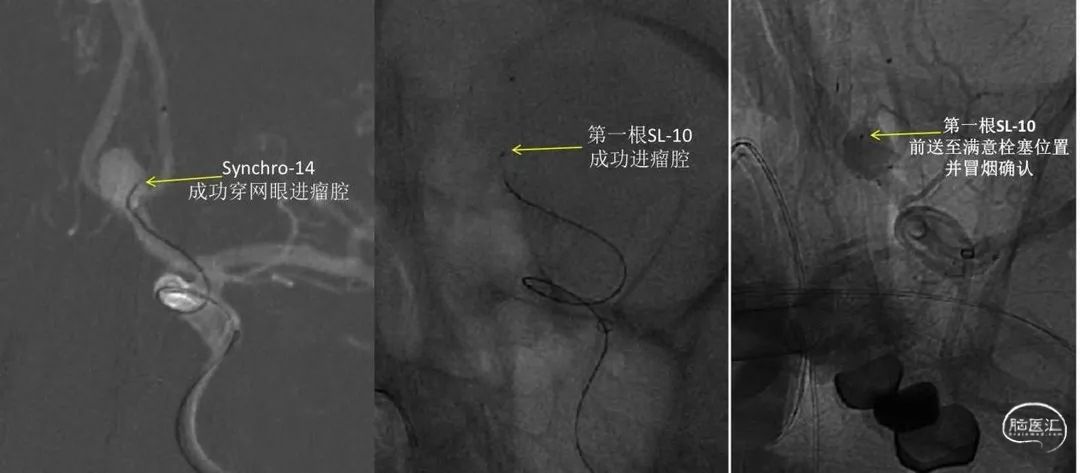

支架释放后,回撤第一根SL-10至大脑前动脉A1段,在Synchro-14微导丝导引下可重新穿支架“网眼”进动脉瘤腔,此时穿网眼并非一层,而是支架上壁及下壁双侧“穿越”。成功后跟进SL-10,并推送至最佳栓塞位置依次进行弹簧圈填塞。

图片6:栓塞微导管(第一根SL-10)到位